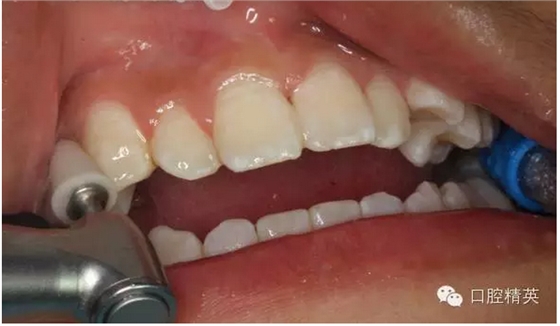

圖8.拆除樹脂夾板

圖9.去除健康牙上的樹脂塊

圖12.拋光粘結(jié)樹脂的牙面

圖13.拋光完畢的牙面,齦乳頭色澤正常,無牙周袋。21不松動